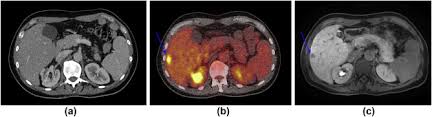

You're right to be concerned. If your doctor orders a computerized tomography scan, you'll be preparing to undergo a ct scan. What you should know before your ct scan we may earn commission from links on this page, but we only recommend products we back. This diagnostic tool is used in many different medical situations, as it gives doctors a way to visualize the body internally to determine the e. A shoulder ct scan will help your doctor see the bones and soft tissues in the shoulder in order to detect abnormalities, such as blood clots or fractures. Optimal Layanan Ct Scan 128 Slice Rsudam Lampung Mampu Periksa 15 Orang Sehari from lampungpro.co Learn about when a ct scan is used for pe, how it works, what it looks like, and more. If a doctor suspects you may have a pulmon. If your doctor orders a computerized tomography scan, yo...